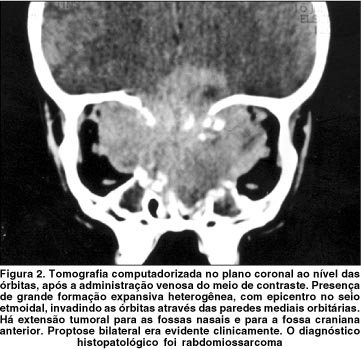

Dos 29 tumores malignos extra-orbitários com complicações oftálmicas (tabela 1), houve predomínio do carcinoma epidermóide (8 casos; 28%) (figura 1), seguido pelo carcinoma basocelular (4 casos; 14%). Linfomas não-Hodgkin, rabdomiossarcomas e carcinomas pouco diferenciados representaram 3 casos cada (10% cada) (figura 2). Os subtipos histológicos dos carcinomas pouco diferenciados e outros sarcomas não puderam ser estabelecidos. As cavidades sinonasais (grupo 1) foram o sítio de origem dos tumores na maioria dos casos (59%), mais comumente o seio maxilar (figura 3), seguidas pelos anexos oculares (grupo 2) em 24% dos casos. Cinco tumores tiveram origem na pele e subcutâneo da face (figura 4).

Aproximadamente 80% de todos os sarcomas de partes moles são rabdomiossarcomas(15), e as cavidades sinonasais podem ser o local de origem destes tumores(21,23). O comprometimento orbitário secundário pode estar associado à proptose e redução da acuidade visual(15,18). Outros sarcomas, como o fibrossarcoma(9), o osteossarcoma(17) e o condrossarcoma(9), também podem cursar com complicações oftálmicas.